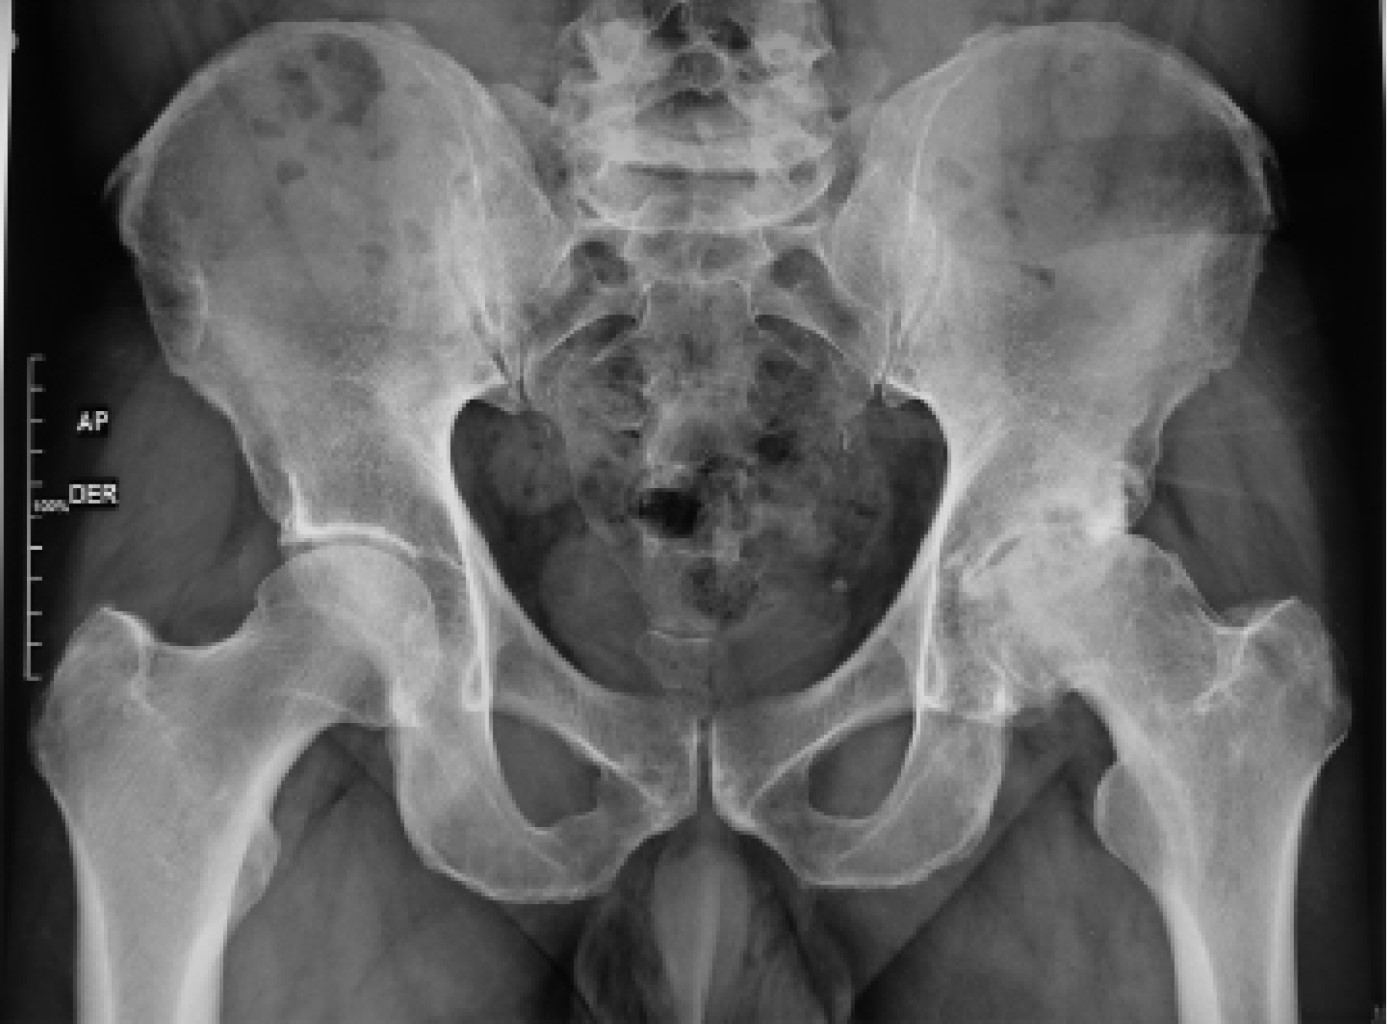

Previa aprobación por los Comités de Investigación y de Ética en Investigación de este hospital (Centro Médico ABC), se efectuó un estudio retrospectivo de todos aquellos casos consecutivos de artroplastía total de cadera, entre Abril de 2018 y Abril de 2020, realizados por abordaje anterior por el mismo cirujano, en el misma institución hospitalaria, igualmente utilizando sistema de reemplazo de cadera con vástago femoral AMIS-H y copa acetabular Versafit-CC (Medacta, Castel San Pietro, Suiza) con liner de polietileno de altos enlaces cruzados y cabeza de cerámica o metal. Se incluyeron 50 caderas en 47 pacientes. Para la totalidad de ellos se formalizó una planificación preoperatoria aprovechando radiografías en proyección anteroposterior con apoyo a una distancia estricta de un metro (Figura 1), proyección anteroposterior de la cadera afectada y proyección oblicua axial a idéntica distancia, así como eje mecánico en la generalidad de los hechos, a excepción de aquellos con fractura de la articulación, a quienes no se les realizó proyección oblicua (Figura 2). Se hizo la medición y selección del tamaño de implantes a utilizar con los sistemas de plantillas específicos de la marca referida. Todos estos afectados tuvieron un seguimiento clínico y radiográfico por 90 días postoperatorios.

Figura 1

Figura 2